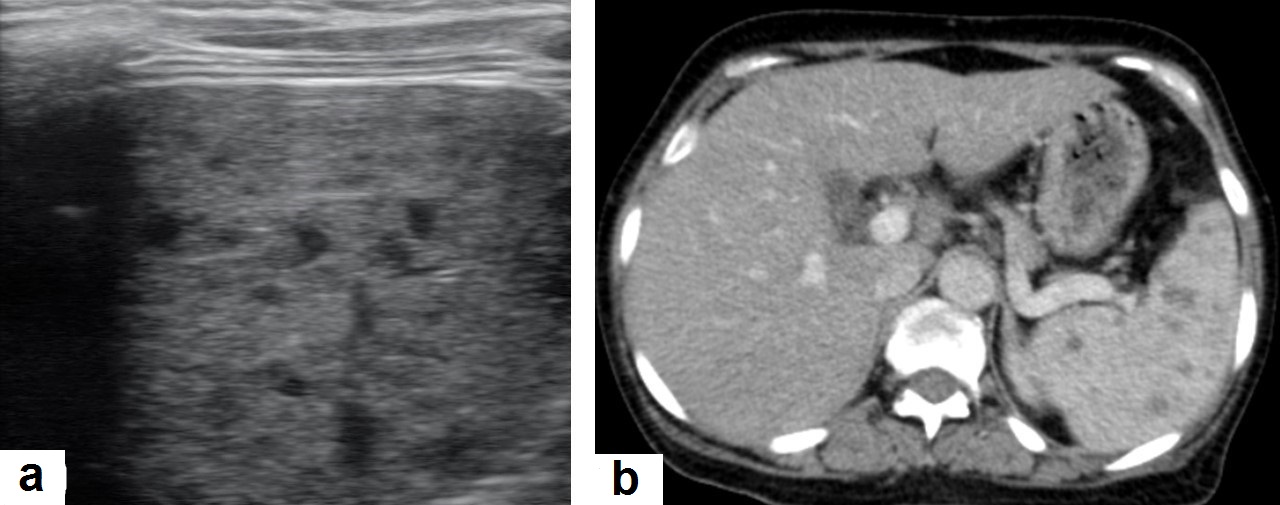

Figure 7. Miliary TB in an adult female with fatigue and loss of appetite. (a) Splenic ultrasonography shows multiple small hypoechoic granulomas with random distribution in the spleen. (b) Axial abdominal CT shows small non-enhancing granulomas with random distribution in the spleen clearly seen during the portal venous phase with multiple enlarged lymph nodes around the portal vein.